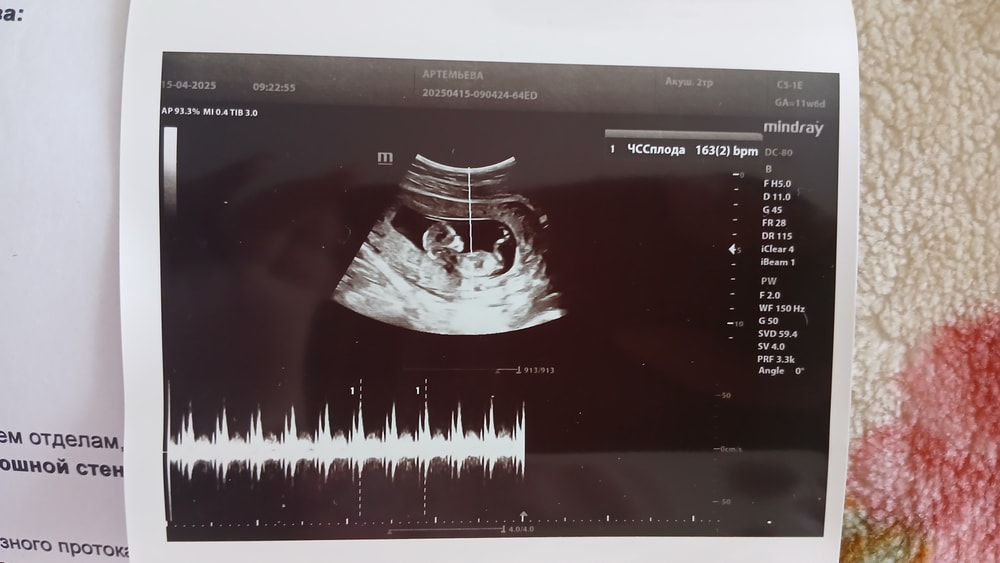

А тут бьется сердечко🥰